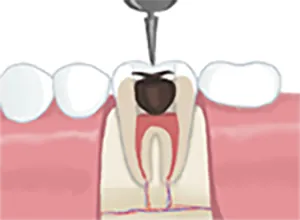

• 虫歯の除去

1虫歯の除去

虫歯になった部分を取り除き、歯の神経があるところまで穴をあけます

• 神経の除去

2神経の除去

細菌が侵入し変質してしまった神経を除去し、神経の通っている穴と根の中の管をきれいに清掃します。